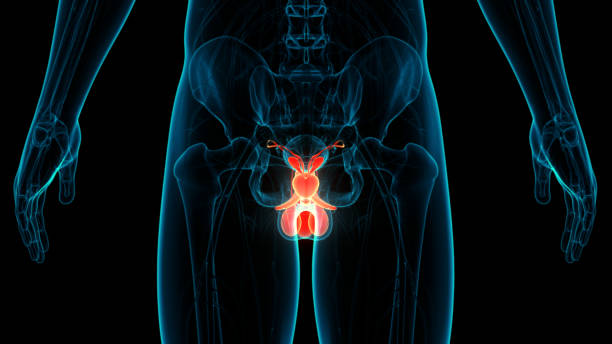

전립선비대증은 남성에서 주로 발생하는 전립선의 비대증입니다. 전립선은 남성의 생식기로서, 요도 주변에 위치하며, 요도를 통해 배뇨와 정액의 배출을 조절합니다. 전립선비대증은 나이가 들수록 발생 확률이 높아지며, 대부분의 남성이 한 번 이상 경험하게 되는 질환입니다.

전립선비대증은 전립선의 세포가 비정상적으로 증식하면서 발생합니다. 이러한 세포 증식으로 인해 전립선이 커지면서 요도 주변을 압박하고, 배뇨와 관련된 증상을 유발합니다. 전립선비대증은 일반적으로 배뇨 불편, 방광염, 자주 병원가는 등의 증상을 유발합니다.